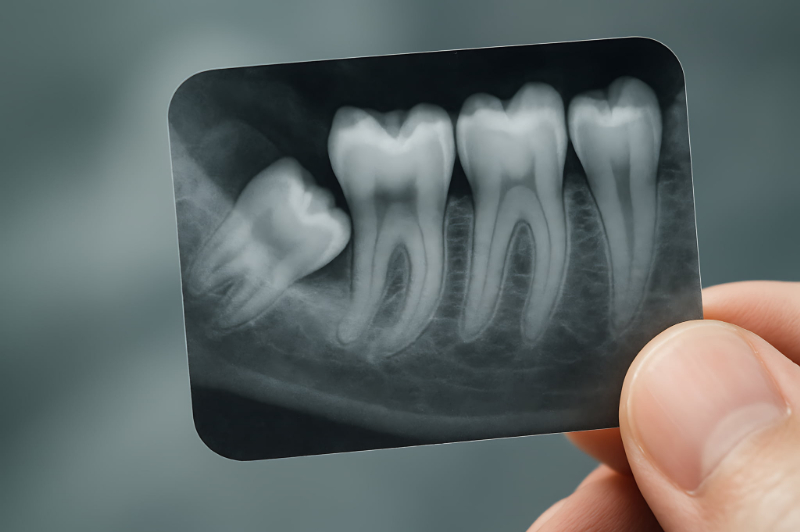

親知らずが横向きや斜めに生えることも多くあります。これは顎のスペースが足りないために起こる代表的なケースです。歯ぐきの中に埋まったまま、見えない状態で横向きになっていることもあります。

親知らずが存在しない、または骨の中に埋まったまま出てこないケースもあります。これ自体は異常ではなく、特に問題がなければそのまま経過観察となることが多いです。

レントゲンを撮ることで、親知らずの状態を確認できます。これによってトラブルを早めに見つけることができれば、将来的にトラブルが起こるリスクを大きく減らすことができます。